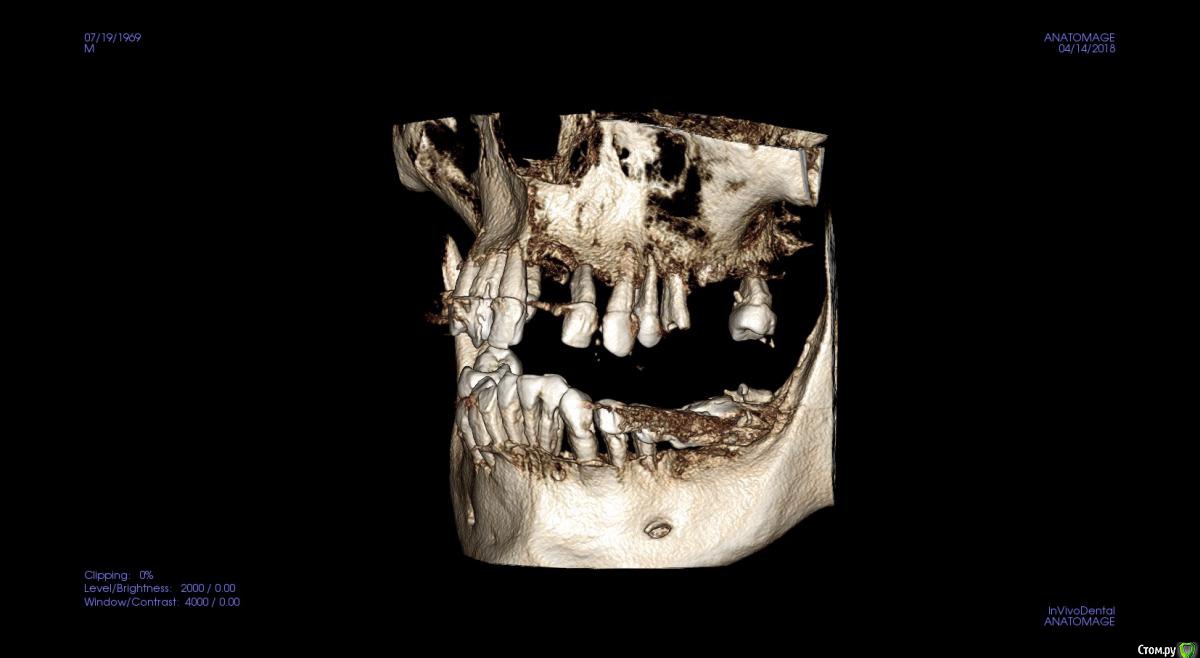

JurJul Опубликовано 17 апреля, 2018 Поделиться Опубликовано 17 апреля, 2018 Не знаю, возможно мой случай в раздел протезирования и не подходит, возможно нужна хирургия и имплантация. История. Живу в Белоруссии. В 2000 году сделал всё, что нужно было: мосты, коронки, виниры на передние зубы. На то время по высокому уровню стоматологии. Где-то через 2 года обнаружили онкологию (семенома) на 1 стадии. Операция, химия, лучевая. Препараты на химиотерапии этопозид, цисплатин. Всё благополучно прошло. Потом где-то через 2-3 года мосты и коронки стали беспокоить и постепенно они снялись. В начале 10-х годов был на нескольких консультациях - сказали, что у меня 2 варианта: ждать пока само всё выпадет и потом ставить всё полностью съемное "под Карегу" и второй вариант - удалять всё раньше и опять же ставить полностью под Карегу. Я как-то не могу с этим смириться, всё же думаю, что возможны варианты ещё, тем более, что научно-технический как и медицина со своими технологиями двигаются семимильными шагами. Про импланты мне говорили, что в моём случае ничего не будет стоять, т.к. была в прошлом химия и лучевая и у меня всё подвижно, что собственно подтверждается состоянием зубов и корней, которые норовят выходить сами. Были частые воспаления дёсен и признаки пародонтоза. В последние месяцы стали шататься передние верхние, прямо похоже как у детей, когда зубы меняются... И вот совсем недавно выпал (помог ему немного) верхний 1-ца. Бисфосфонаты не принимал. Зубы после онко удалял. Лунки заживали нормально.В субботу 14.04 был на консультации у имплантолога. Ведущий специалист в этой области в РБ... во всяком случае так его позиционирует Гугл )) Так вот мне сразу был предложен самый оптимальный в моём случае вариант - всё на 6 на обе челюсти и всё сразу и быстро. Удаляем всё и сразу и тут же вкручиваем импланты (Израиль или Нобель). Через 5-7 дней ставим временный несъемный протез и через полгода вуаля постоянный несъемный (либо керамику либо цирконий по желанию). Типа это в моём случае самое оптимальное и не очень тяжёлое в физическом и психологическом плане (сразу с зубами, не нужно съёмный протез полгода носить или без зубов долго ходить )... Я, честно говоря, не готов на такой вариант... Я понимаю, что возможно хороших зубов, которые смогут служить опорой под мост/ы, может и нет. И, возможно, и нужно будет всё удалить... Но я думаю, может и ошибаюсь, что есть и др. методы имплантации, если это неизбежно. Как мне сказали на консультации, что предложенный вариант единственный для верхней челюсти, варианты могут быть по низу, но по верху - без вариантов...Озвучена по стоимости работа "под ключ" : с израильскими имплантами 12 тыс. дол. , с американскими 20 тыс. дол. Дело даже не в стоимости. Просто мне не хотелось бы стать одним из авторов стом. форумов с мольбой о помощи в исправлении чьей-то работы с имеющимися проблемами. Больше всего на свете я не хочу проблем и переделок. Я понимаю, что на 100% нельзя быть уверенным в результате, но минимизировать риски, выбрав самый лучший или оптимальный вариант, можно. Вот поэтому я решил обратиться сюда за консультацией. Ссылка на 3D томографию: https://drive.google.com/open?id=1puDkkPZG_C-UQCklhUjX5sdAS_SOIooZВзываю к помощи товарищей врачей! Только на вас уповаю Ссылка на комментарий

St. Опубликовано 17 апреля, 2018 Поделиться Опубликовано 17 апреля, 2018 Обзорные срезы ( верх, низ, топография нижнечелюстного нерва), дефект в обл 21 Ссылка на комментарий

kozloff Опубликовано 18 апреля, 2018 Поделиться Опубликовано 18 апреля, 2018 План действий.Удаление зубов.Повторное КТ.Рекомендуется костная пластика.Имплантация по шаблону. Ссылка на комментарий